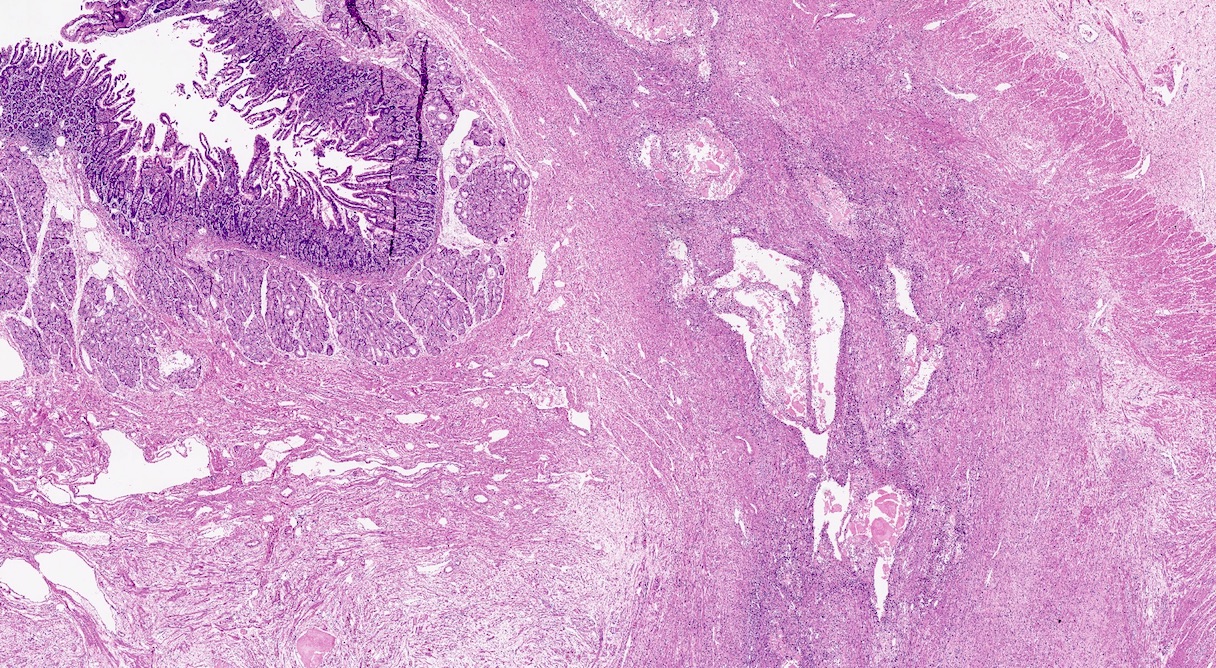

Gross description

- Whitish parenchyma with extensive fibrosis, dilated ducts and calculi

- Fibrotic parenchyma retains a lobulated appearance

- In advanced stages, a reduction in the volume of the pancreatic gland may occur

- Parenchymal and intraductal calcification are typical and often grossly appreciable

- Pseudocysts are more common in alcoholic pancreatitis, whereas obstructive pancreatitis shows retention cysts (Pathologica 2020;112:197)

- Paraduodenal pancreatitis may show cystic change near the minor ampulla and trabeculated fibrosis centered around the duodenal wall (Semin Diagn Pathol 2004;21:247)

Gross images

Microscopic (histologic) description

- Triad of cardinal features: fibrosis, loss of acinar tissue, duct changes (Pancreatology 2020;20:586)

Microscopic (histologic) images